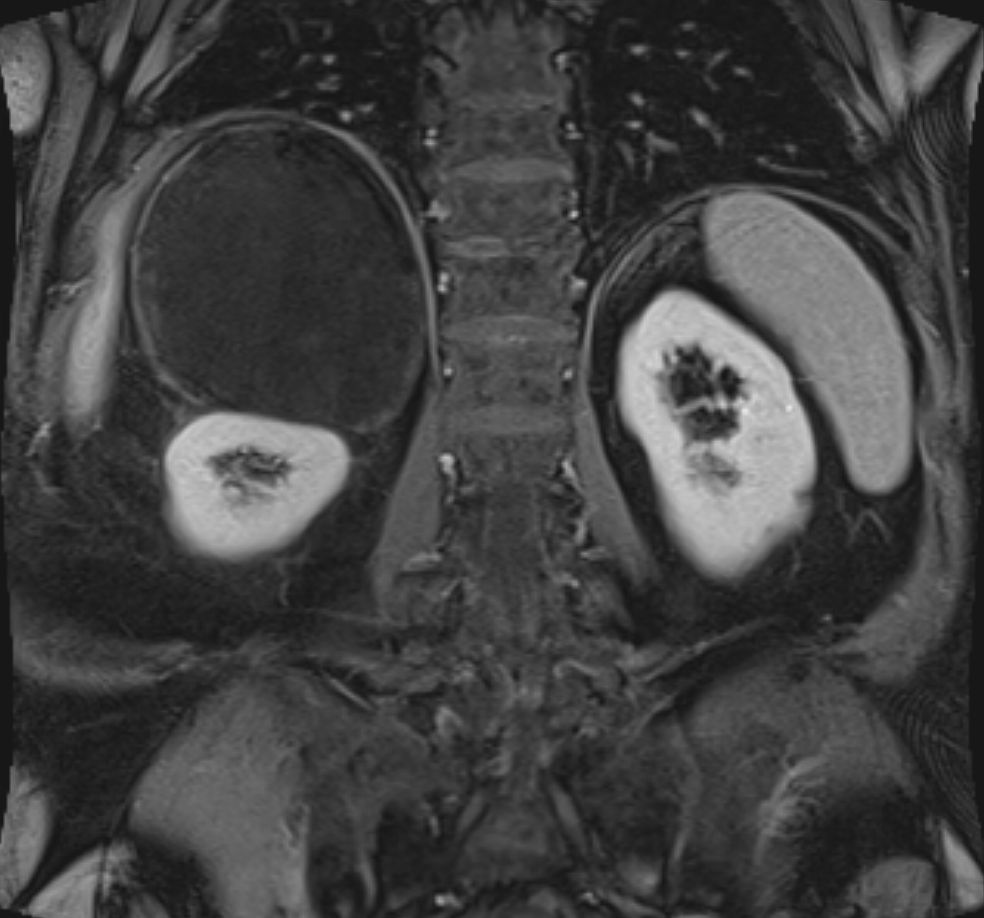

79-jähriger berenteter, adipöser Fleischer mit respiratorischer Insuffizienz. Urothel-Ca vor 15 Jahren.  Jetzt kleines Bronchial-Karzinom. Beim Tumorstaging wurde ein großer NN-Tumor rechts entdeckt.  | |||